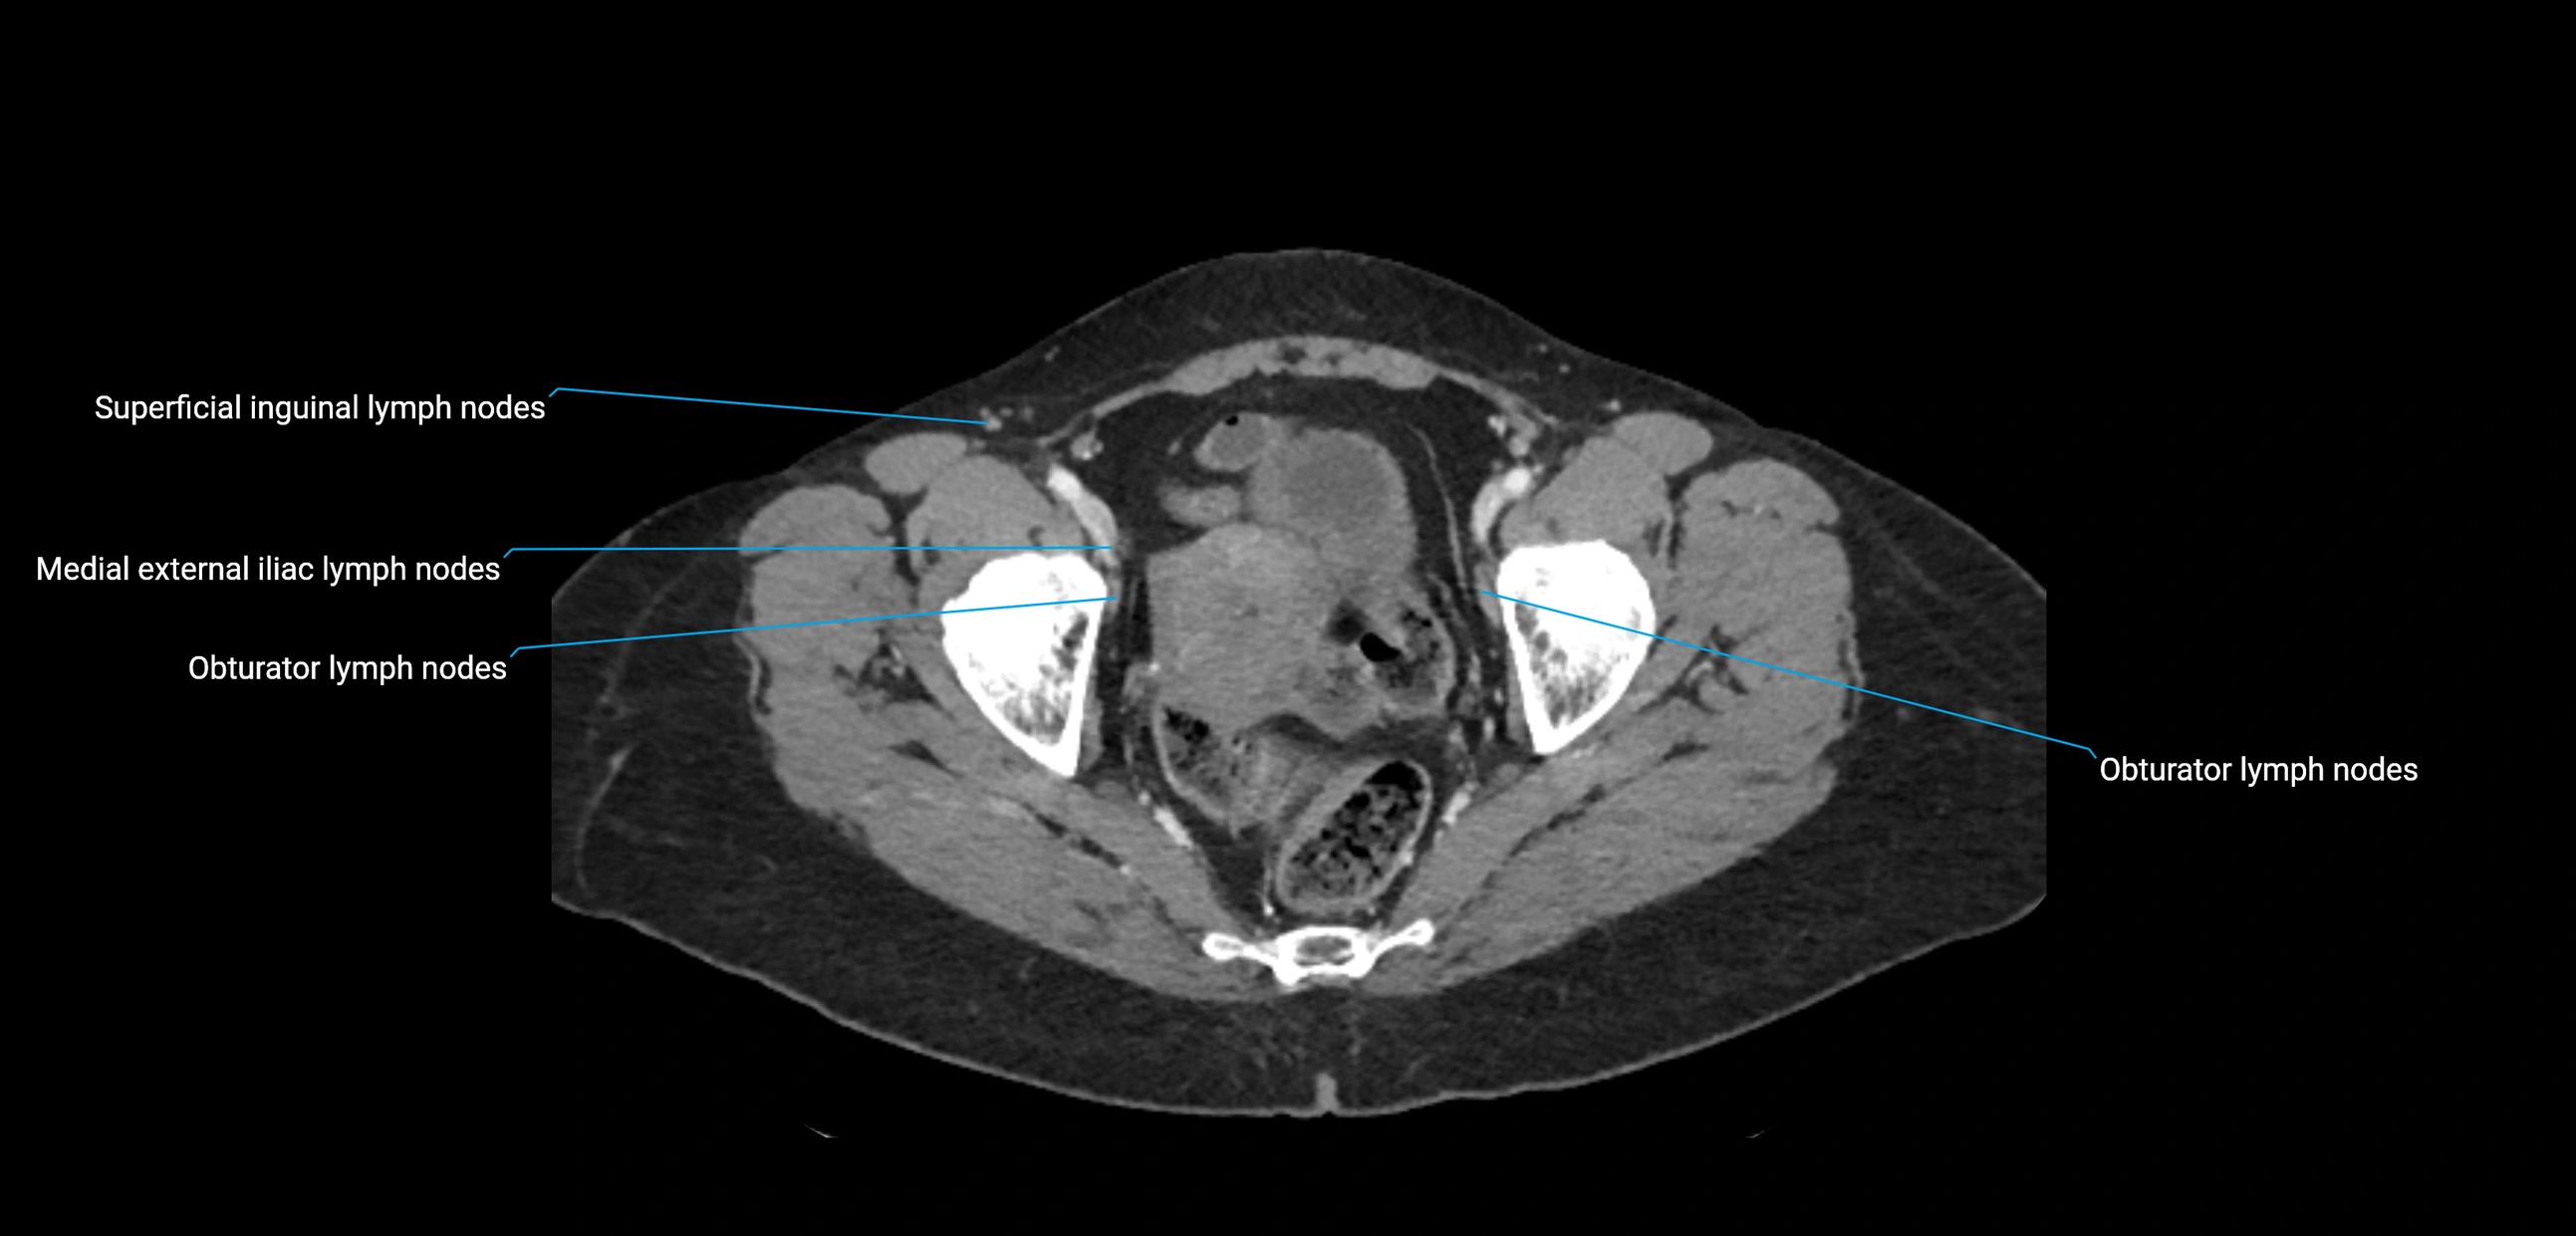

CT image

image